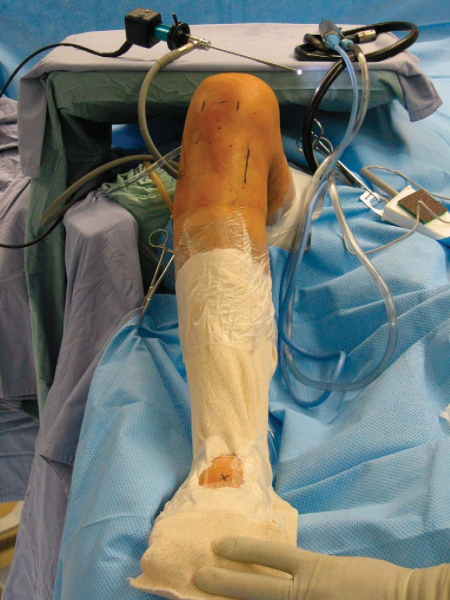

An examination under anesthesia is then performed. The nonoperative knee is examined, followed by the operative knee. The alignment and range of motion are assessed with specific attention to terminal extension and flexion. A thorough ligamentous examination is conducted to determine the patterns of laxity. Once the leg is prepared and draped, the dorsalis pedis artery is palpated and marked, and a hole is cut in the stockinette for access to the pulse throughout the case (

Fig. 71-2

).